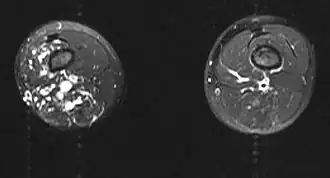

| Imagem por ressonância magnética | |